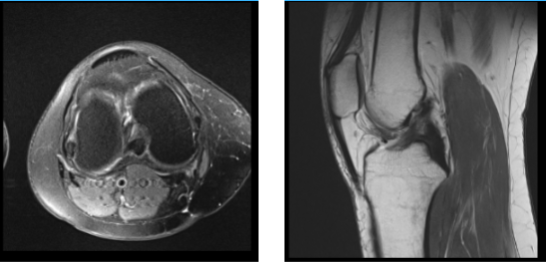

MRI were reviewed and discussed; Collateral Ligaments: The medial collateral ligament is intact. The lateral collateral ligament, biceps femoris tendon, iliotibial band, and popliteus tendon is intact.

Cruciate Ligaments: The anterior and posterior cruciate ligaments are intact. Menisci: Peripheral oblique tear in the body and posterior horn the medial meniscus. The lateral meniscus is intact. Cartilage: The chondral surfaces in the medial compartment are intact. The chondral surfaces in the lateral compartment are intact.

Focal chondral fissure in the medial patellar facet. Bones: The visualized osseous structures demonstrate normal bone marrow and cortical signal intensity without evidence of fracture, trabecular bone injury or dislocation. No osseous lesions are identified.

Extensor Mechanism: The quadriceps and patellar tendons are normal. Joint: Small joint effusion. The soft tissues are otherwise normal. The neurovascular structures demonstrate normal course. It has an impression: Peripheral oblique tear in the body and posterior horn of the medial meniscus. Focal chondral fissure in the medial patella facet. Small joint effusion.

MRI Right Knee Non-contrast